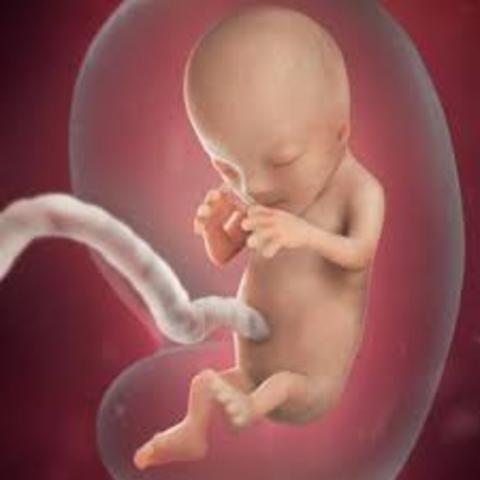

• 2nd Trimester

Length of Time: 13-27 weeks

• 4th Month

4th Month

1. You can feel the baby move.

2. The baby's skin is pink.

3. The umbilical cord and placenta works.

• 5th Month

5th Month

1. The baby moves a lot.

2. Weighs 8 ounces.

3. The baby will sleep in your belly.

• 6th Month

6th Month

1. Eyes are fully developed.

2. The baby can hear.

3. Taste buds form.